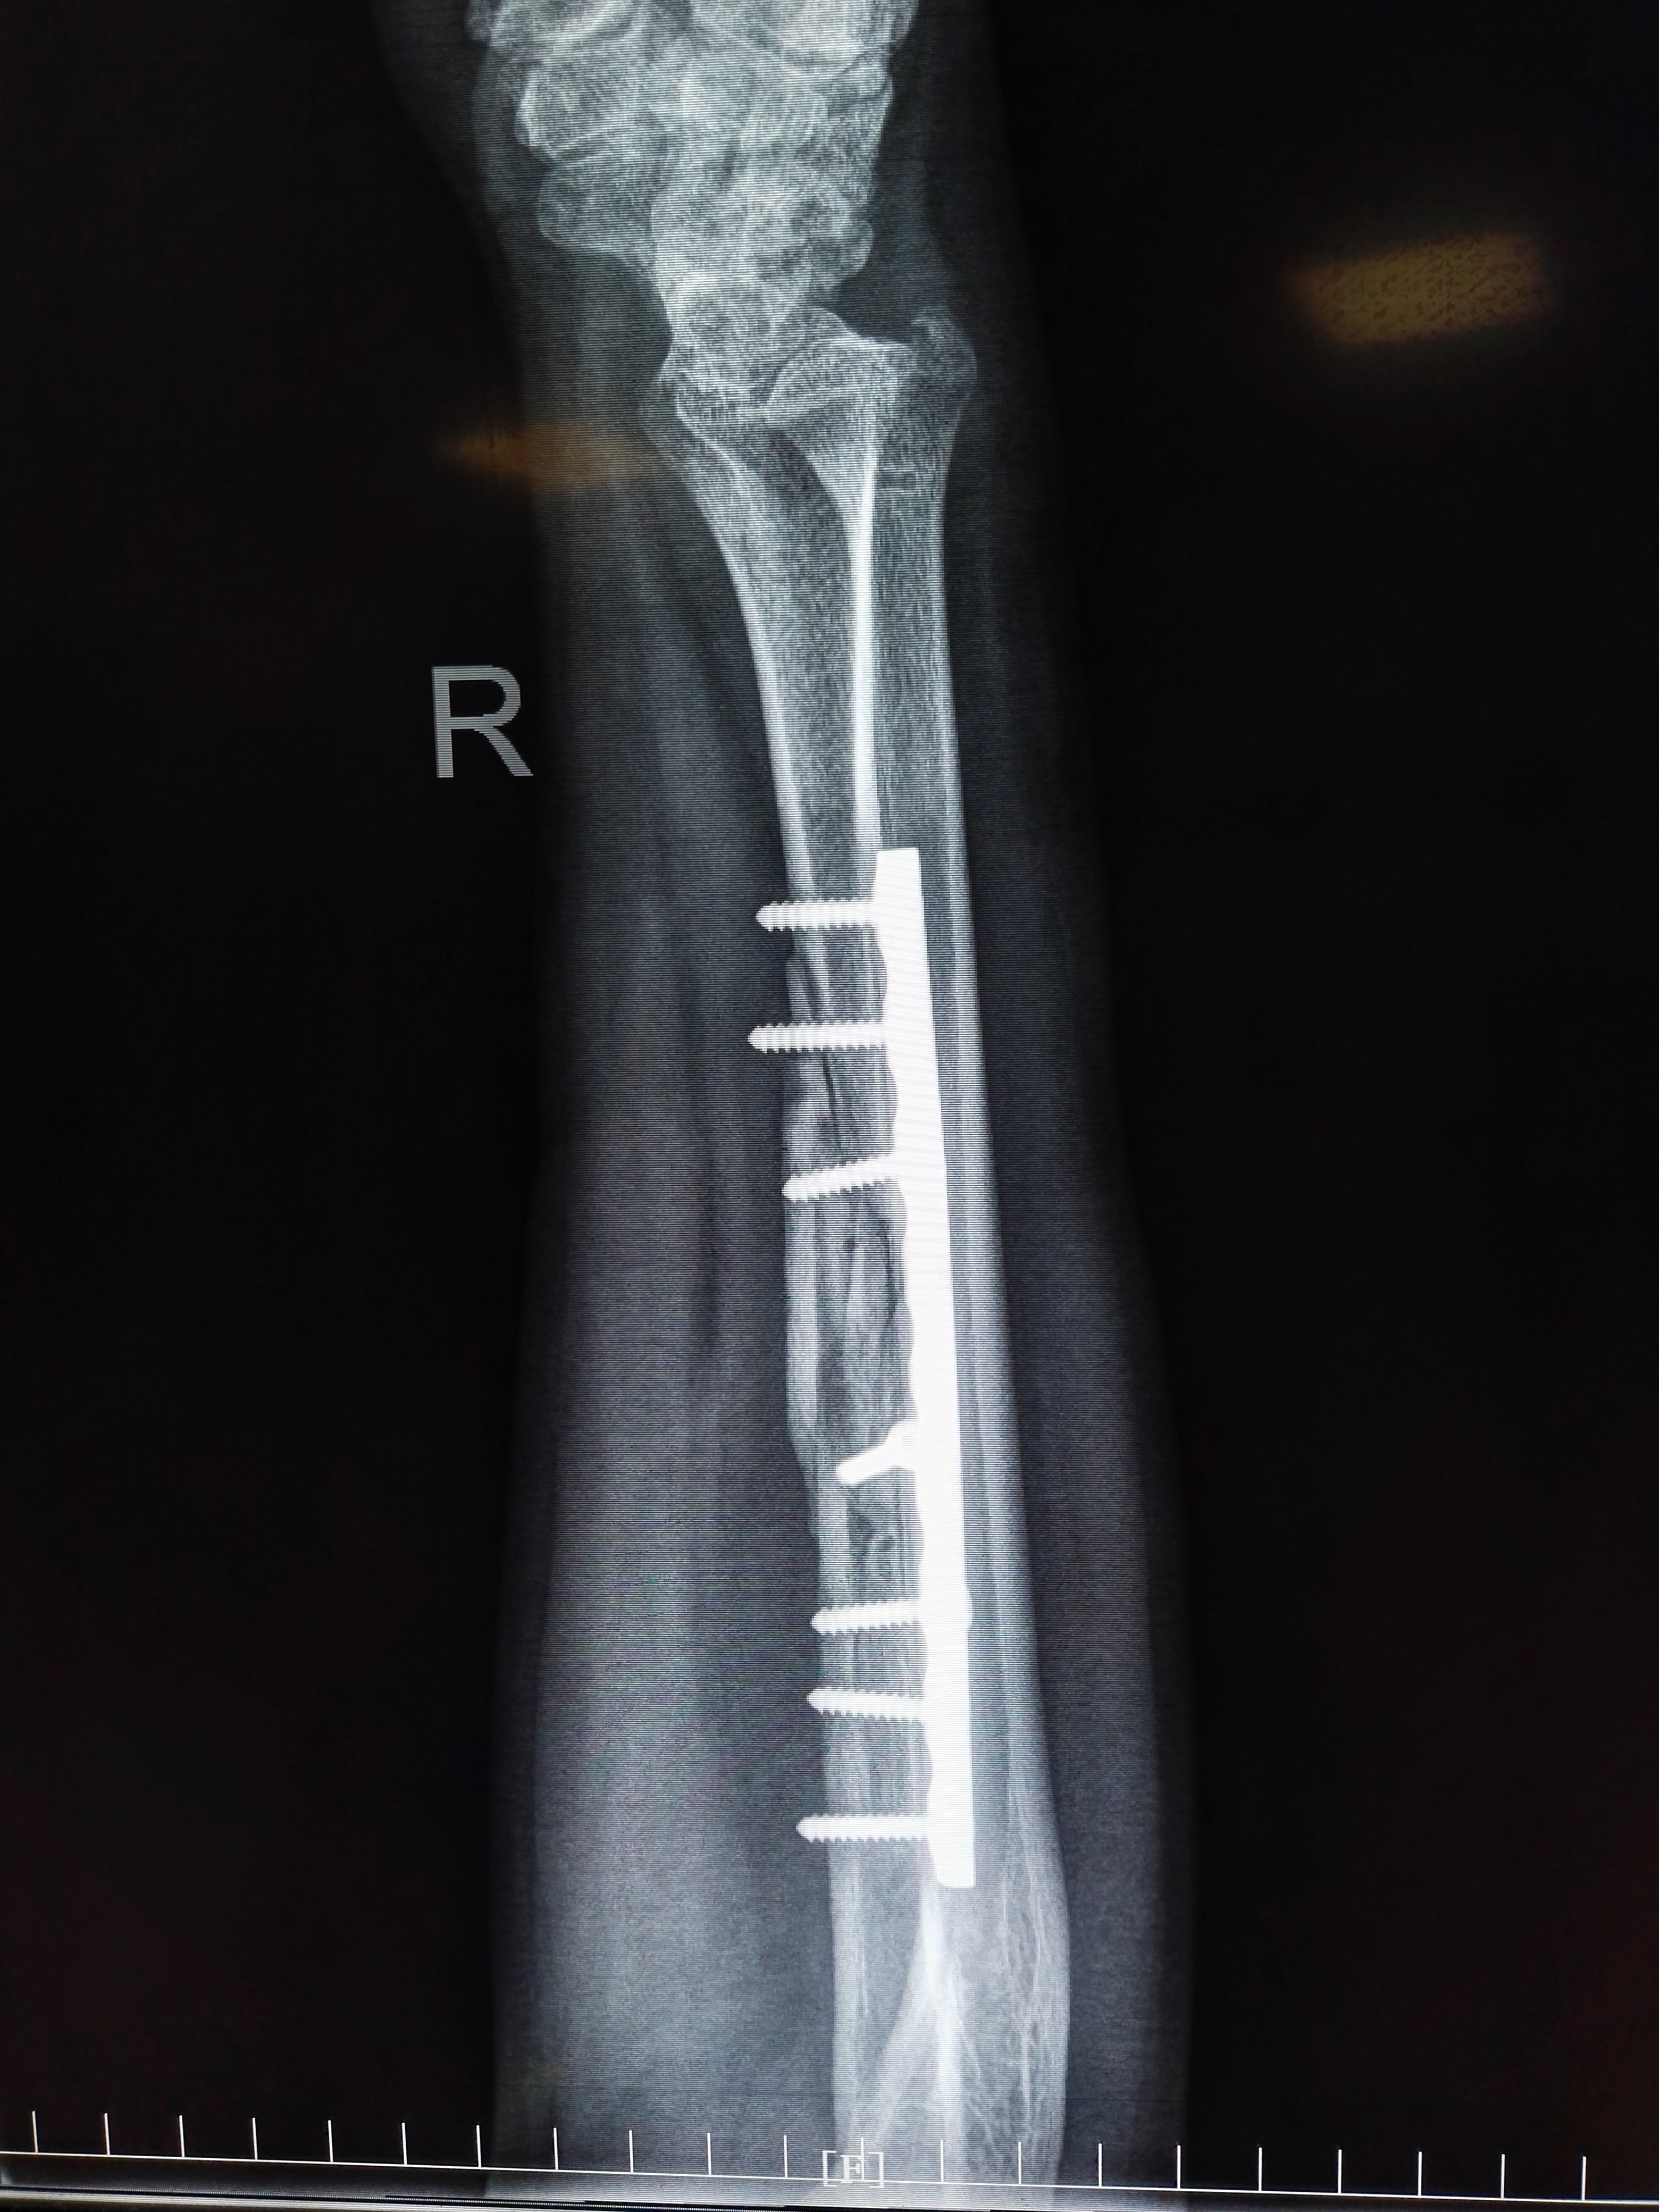

右侧尺骨骨折